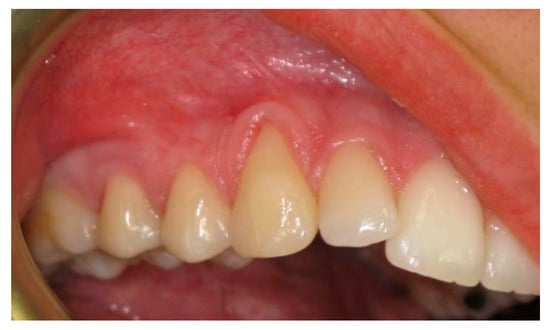

Laterally Positioned Flap Procedure with Augmented or Nonaugmented Palatal Connective Tissue Grafts in the Treatment of Multiple Adjacent Gingival Recessions: A Two-Year Follow-Up Study

:1. Introduction

2.3. Surgical Procedures